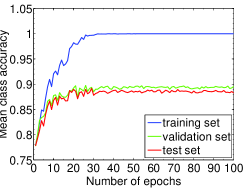

We highlight that training-relevant hyper-parameters can significantly affect the convergence of cost function, the learning speed and the generalization capability of the network. Their impacts are demonstrated via the learning curves of MCA on training, validation and test sets shown from Fig. 4 to Fig. 8. In each figure, we focus on one hyper-parameter while the others are set to their optimal values in Table 2.

Fig. 4 LABEL:sub@subfig:lr1 indicates that when learning rate is small, e.g., , the learning process is so slow that the MCA of the three sets have not become stable in epochs. Properly increasing the learning rate effectively improves learning efficiency and the MCA becomes stable in epochs, as shown in Fig. 4 LABEL:sub@subfig:lr2. At the same time, an over-large learning rate, e.g., , will destabilize the learning process and degrade the classification performance. Also, Fig. 5, 6 and 7 demonstrate the impacts of mini-batch size, momentum and weight decay, respectively.